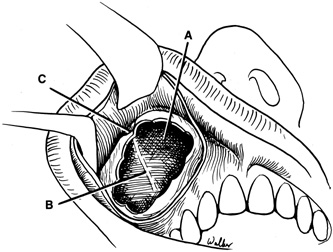

surface of the lateral rim.  Fig. 7. Coronal schematic view demonstrating major vessels penetrating periorbita

and traversing the extraperiosteal space that may be encountered during

periorbital elevation. (A, zygomaticotemporal artery; B, zygomaticofacial artery; C, communicating branch of infraorbital artery: D, supraorbital artery: E, posterior ethmoidal artery: F, anterior ethmoidal artery.) Fig. 7. Coronal schematic view demonstrating major vessels penetrating periorbita

and traversing the extraperiosteal space that may be encountered during